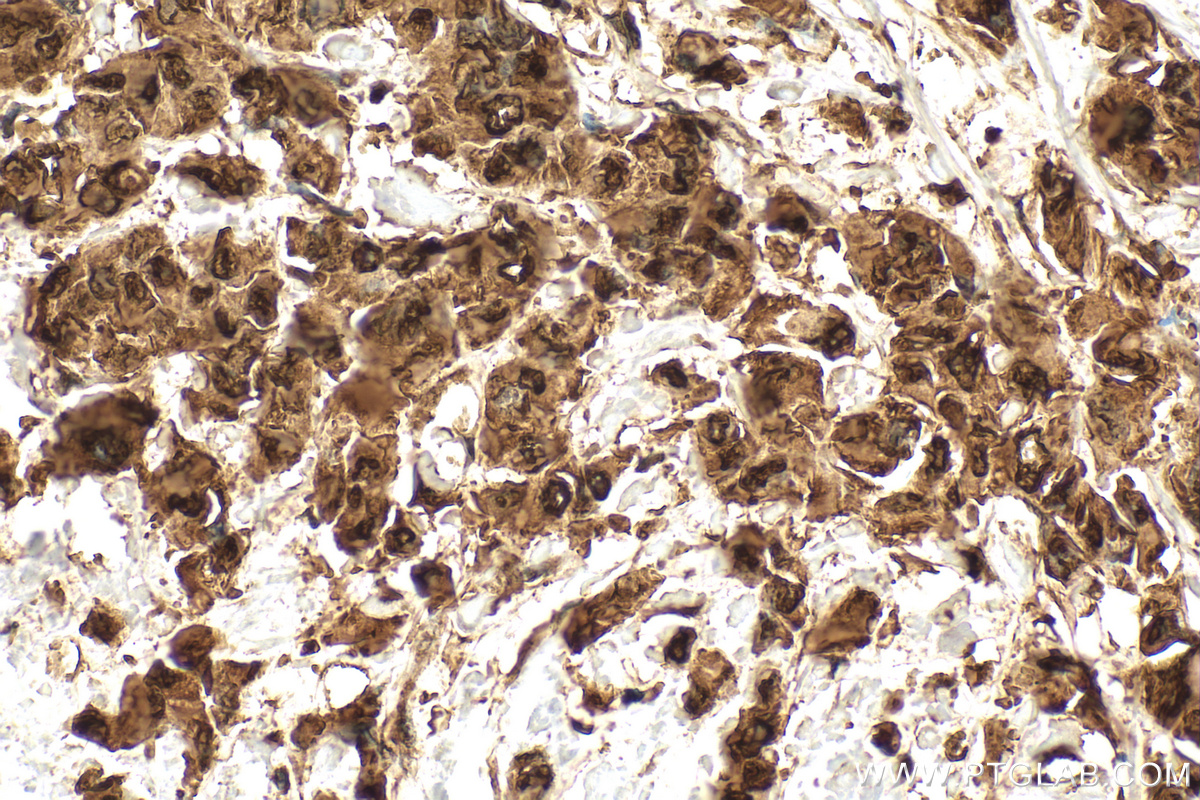

| Positive IHC detected in | human liver cancer tissue, mouse skin tissue, human breast cancer tissue, human colon tissue Note: suggested antigen retrieval with TE buffer pH 9.0; (*) Alternatively, antigen retrieval may be performed with citrate buffer pH 6.0 |

| Immunohistochemistry (IHC) | IHC : 1:1000-1:4000 |